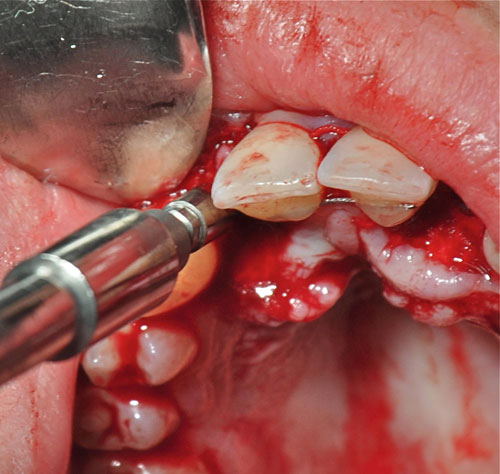

Abordamos con fresa lanceolada para el marcaje del lecho y expandimos con expansores roscados para densificar un hueso de Tipo IV

Realizamos un colgajo vestibular y palatino sin incisión de descarga para preservar lo mas posible el aporte sanguíneo

Instalación de implantes

Instalación de implantes

Instalación de implantes

Instalación de implantes

Tallado de los Abbutments